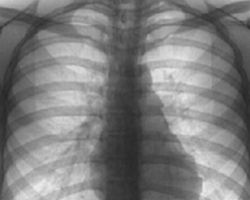

Ни одно инфекционное заболевание не уносит столько жизней украинцев, как туберкулез. Свиной грипп, дифтерия и столбняк, вместе взятые не сравнятся с масштабами эпидемии туберкулеза. Каждый день в нашей стране туберкулез уносит около 25 жизней. И, несмотря на то, что эта проблема «государственная» особых изменений в лучшую сторону не наблюдается. Единственным заметным участием государства в решении проблемы туберкулеза является внедрение плановой флюорографии. И, несмотря на скромные возможности флюорографии, она, бесспорно, способствует выявлению новых случаев заболевания.

В основе флюорографии лежит использование рентгеновского излучения, которое, пройдя через ткани человека, фиксируется на пленке. По сути, флюорография - это максимально удешевленное рентгенологическое исследование органов грудной клетки, целью которого является массовое обследование и обнаружение патологии. В приказе МОЗ Украины есть фраза - «обнаружение на ранних стадиях». Но, к сожалению, весьма сомнительной является возможность ранней диагностики любого заболевания на снимке размером 7х7 см, пусть даже увеличенном на флюороскопе. Да, метод далек от совершенства и довольно часто дает погрешности, но на сегодняшний день остается незаменимым.

Результаты флюорографии

Изменения на флюорограмме, как и на любом рентген-снимке, преимущественно вызваны изменениями плотности органов грудной клетки. Только в том случае, когда имеется определенная разница между плотностью структур, рентгенолог сможет увидеть эти изменения. Чаще всего рентгенологические изменения вызваны развитием соединительной ткани в легких. В зависимости от формы и локализации, такие изменения могут быть описаны как склероз, фиброз, тяжистость, лучистость, рубцовые изменения, тени, спайки, наслоения. Все они являются видимыми благодаря повышению содержания соединительной ткани.

Несмотря на достаточно высокую степень погрешности флюорографии, нельзя не признать эффективность этого метода в диагностике туберкулеза и рака легких. И как бы нас не раздражали порой необъяснимые требования прохождения флюорографии на работе, в институте или где-либо, отказываться от нее не стоит. Часто, только благодаря массовой флюорографии, удается выявлять новые случаи туберкулеза, тем более что обследование проводится бесплатно.

Особую актуальность флюорография имеет у нас в Украине, где с 1995 года объявлена эпидемия туберкулеза. В таких неблагоприятных эпидемиологических условиях все мы находимся в группе риска, но, в первую очередь, это люди с иммунодефицитами, хроническими заболеваниями легких, курильщики, и, к сожалению, дети. Кроме того, занимая лидирующие мировые позиции по табакокурению, мы довольно редко соотносим этот факт с туберкулезом, а зря. Курение, несомненно, вносит свой вклад в поддержку и развитие эпидемии туберкулеза, ослабляя, в первую очередь, дыхательную систему нашего организма.

Подводя итоги, хотим еще раз заострить Ваше внимание, что ежегодная флюорография может оградить Вас от смертельно-опасных болезней. Так как вовремя обнаруженный туберкулез и рак легких - порой единственный шанс на выживание при этих заболеваниях. Берегите здоровье!